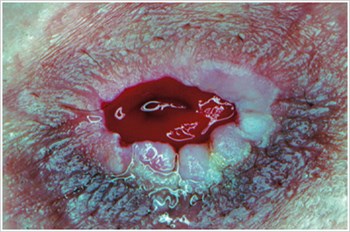

Piyoderma Gangrenozum

Açıklama/Nedenler:

Crohn hastalığı veya ülseratif kolit gibi inflamatuar bağırsak hastalığı (IBH) olan hastalarda sıklıkla görülen inflamatuar bir cilt hastalığı.

Belirtileri:

• Düzensiz şekilli, kırmızı, ağrılı, enfekte ülserler, kırmızıdan mora yuvarlanmış kenarlar; bacaklarda, kalçalarda, yüzde ve peristomal bölgede görülür.